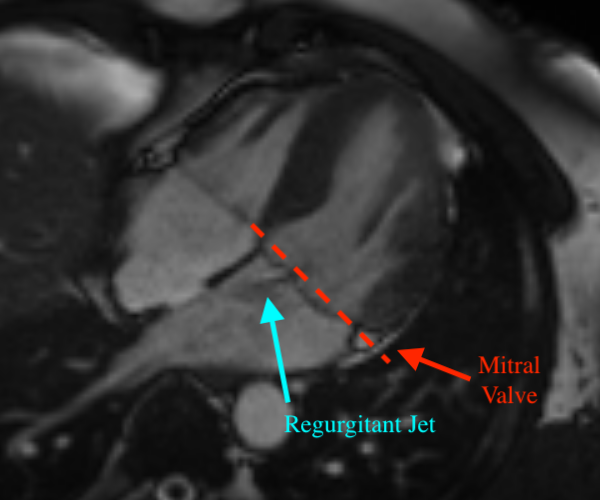

Mitral regurgitation (MR) [7] is a valvular heart disease in which the mitral valve does not close completely during systole when the left ventricle contracts, causing regurgitation – leaking of blood backwards – from the left ventricle (LV), through the mitral valve, into the left atrium (LA) – Figure 1. MR can be caused by either organic or functional mechanisms [6], with organic MR leading to atrial and annular enlargement and functional MR increasing atrial pressure. As MR progresses, it may cause arrhythmia, shortness of breath, heart palpitations and pulmonary hypertension [14]. Left undiagnosed and untreated, MR may cause significant hemodynamic instability and congestive heart failure which can lead to death [17], while acute MR usually necessitates immediate medical intervention [22]. Thus, early detection and assessment of MR are crucial for optimal treatment outcomes, with the best short-term and long-term results obtained in asymptomatic patients operated on in advanced repair centers with low operative mortality (<1%absentpercent1<1\%) and high repair rates (8090%absent80percent90\geq 80-90\%[7].

Figure 1: Three cardiovascular magnetic resonance (CMR) images showing the long-axis four-chamber view of the heart. Left: a heart with normal mitral valve. Middle: a heart with normal mitral valve when the valve leaflets are open. Right: a heart with mitral regurgitation. The red dotted line denotes the mitral valve.